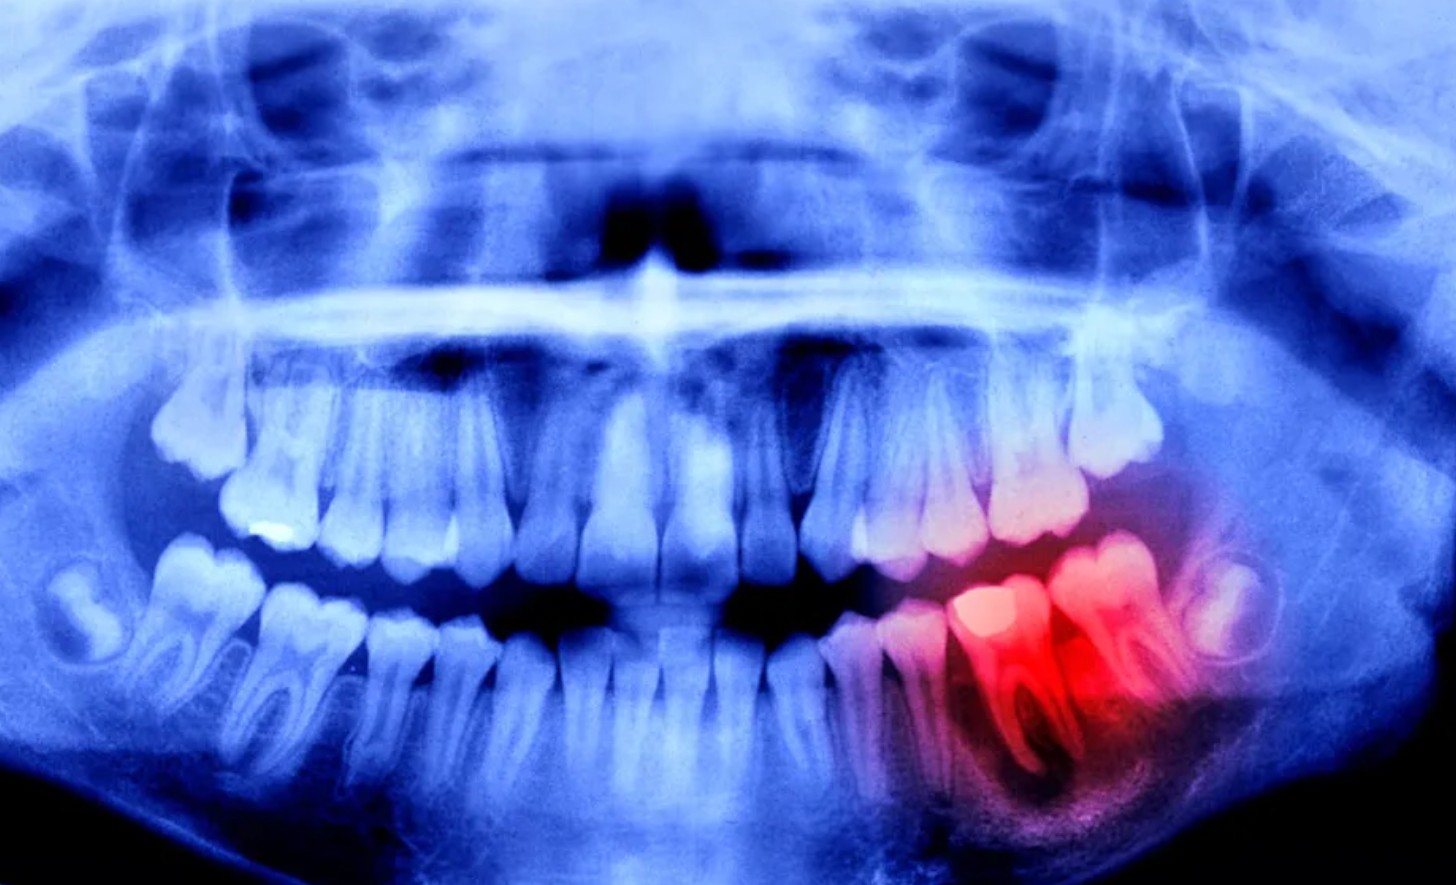

Лек за раст на заби, нешто што до вчера звучеше како научна фантастика, влегува во човечка фаза на тестирање во Јапонија – но со јасно ограничување: прво се таргетираат случаи на недостиг на заби (вроден или делумен), а не „поправка“ на секој скршен заб или кариес.

Терапијата е антитело што го блокира USAG-1 – протеин поврзан со кочење на растот на забите. Идејата е да се „ослободи“ сигнализацијата што ја води забната морфогенеза (особено преку BMP патеката), но без директно мешање во пошироките механизми што влијаат на целото тело. Претклиничките резултати што ја туркаа приказната напред доаѓаат од животински модели: кај глувци и порови е покажано дека блокирањето на USAG-1 може да поттикне формирање нов заб.